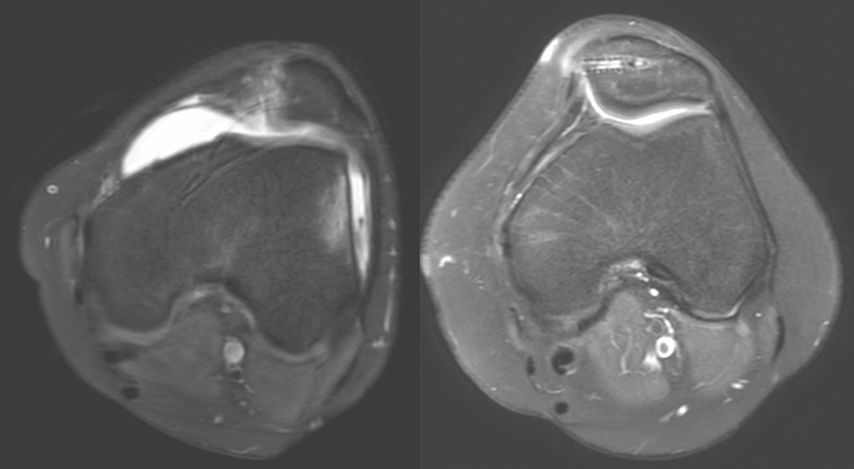

Eine Instabilität bis circa 30° ohne weitere Auffälligkeiten in der radiologischen Untersuchung wird mittels alleiniger MPFL-Rekonstruktion stabil. Ab circa 0–60° Instabilität gibt es zumeist Probleme mit der knöchernen Führung. Dies kann aufgrund eines zu späten Eingleitens der Patella – einer Patella alta – und/oder des Fehlens einer knöchernen Führung (Trochleadysplasie) auftreten. Unserer Meinung nach bedarf es einer Korrektur der Patella alta ab einem Caton-Deschamp-Index >1,2 (Abb.1) und/oder einer LTI (laterale Trochleainklination) von <17° (Abb. 2). Ab 60° ist zusätzlich ein Problem im Bereich des Alignments wahrscheinlich. Bei einer vermehrten Innenrotation des Femurs und der Tibia bei ca. 35° und/oder valgischer Beinachse ab ca. 5° wird eine Korrektur in Erwägung gezogen (Abb.3). Prinzipiell sind wir bei einer Alignmentkorrektur eher zurückhaltend (von manchen Autoren wird bereits eine Korrektur ab 20° Innenrotation empfohlen).5 Ein vermehrter TTPCL-Abstand (lateraler Kraftvektor der Patella) ab circa 24mm kann die Luxation ebenfalls begünstigen und bei einer Patella alta mitkorrigiert werden. Sollte eine knöcherne Stabilisierung notwendig sein, ist bei der Trochleaplastik eine arthroskopische oder offene Technik möglich.

Ablauf der arthroskopischen Trochleaplastik